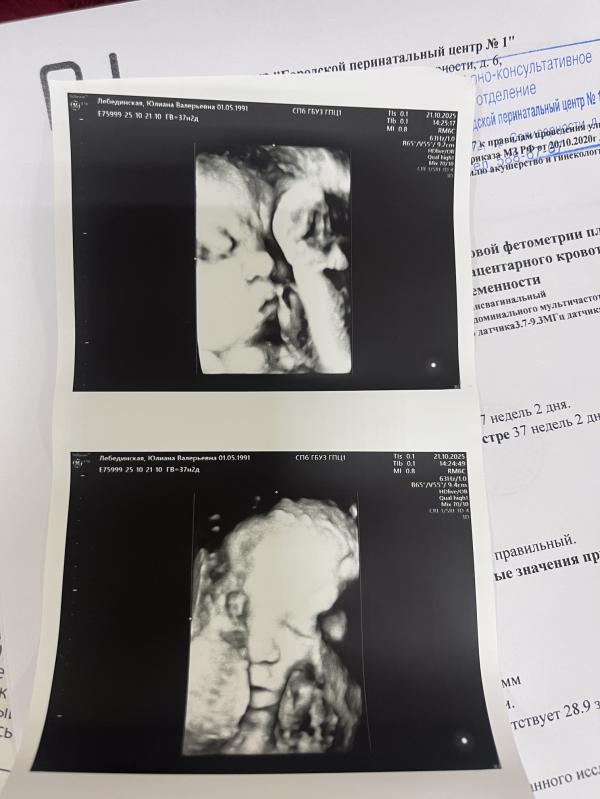

Скажите мне, что я не единственный человек, у которого нет ни одной беременной фотосессии (в этот раз)? Вот не люблю фотографироваться, позировать, неловко чувствую себя перед камерой. Сын, видимо, такой же - первый раз за всю беременность показал личико! На каждом узи закрывался от датчика, и до сегодняшнего дня у нас с ним не было ни одного 3д- снимка!